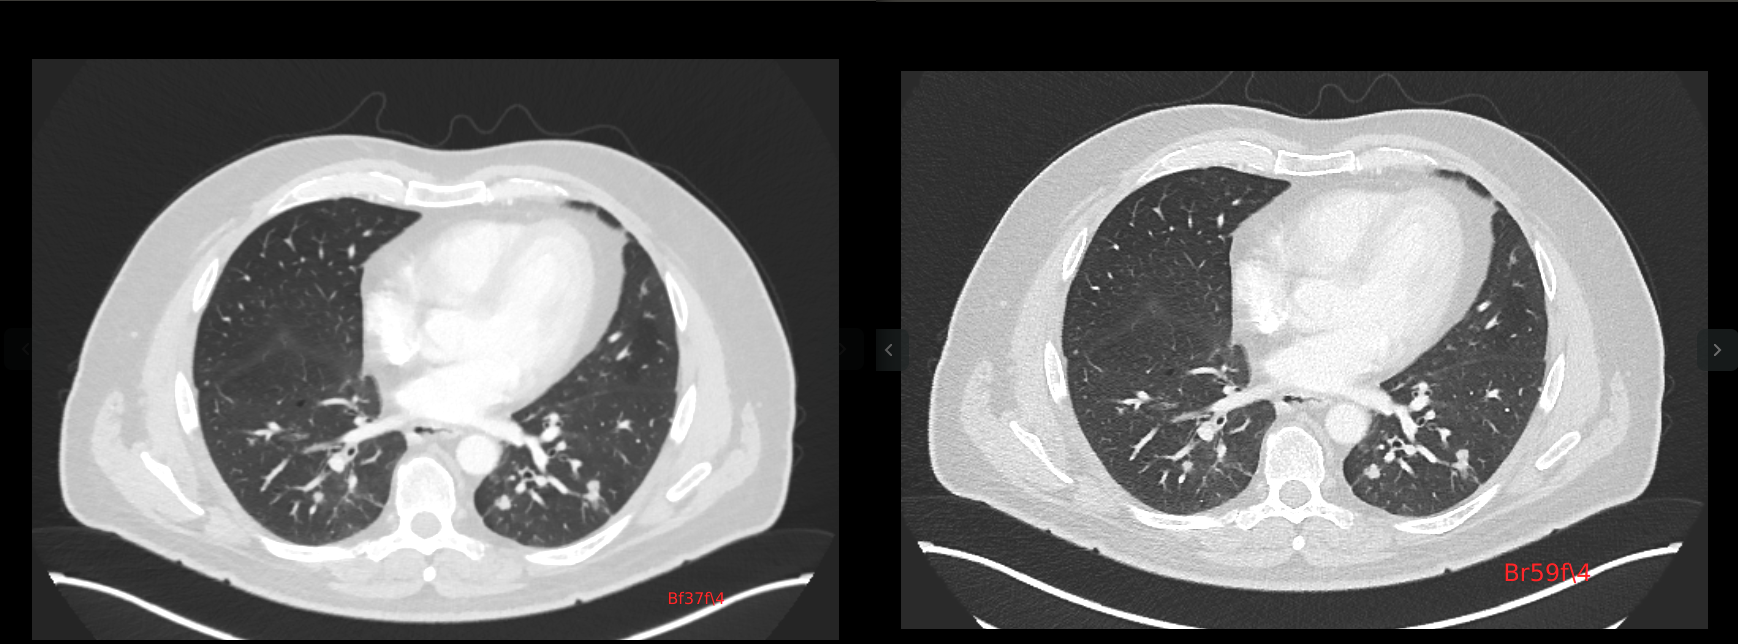

我们可以通过看它的轴状位的图像,来加以观察和对比。

如果仔细观察这两个序列上面,某一个轴位图上面的差异,可以看出。第二幅图(Br59f\4)的图,它的细节,相比第一幅图(Bf37f\4)的图,更明显。

第一幅图,比较平滑,但是细节不够明显; 第二幅图,就像在第一幅图的基础上,做了一个边缘提取和锐化的操作。就是让它的边缘更加的明显,对比度更加强。

而第一幅图,相当于是在第二幅图的基础上,做了一个高斯滤波,去掉了很多噪声,得到了更加平滑的图像。